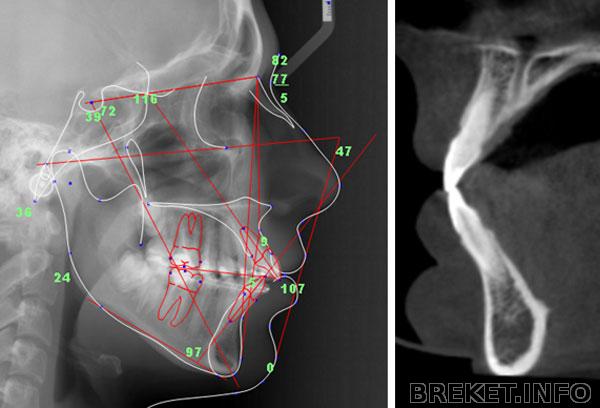

90 - это не норма, резцы действительно не должны стоять прямо. Измеряют наклон не на глазок, а по ТРГ, например так:

Конечно, когда "веер" это и без ТРГ видно, но я вот по фото не вижу ничего выпиющего.